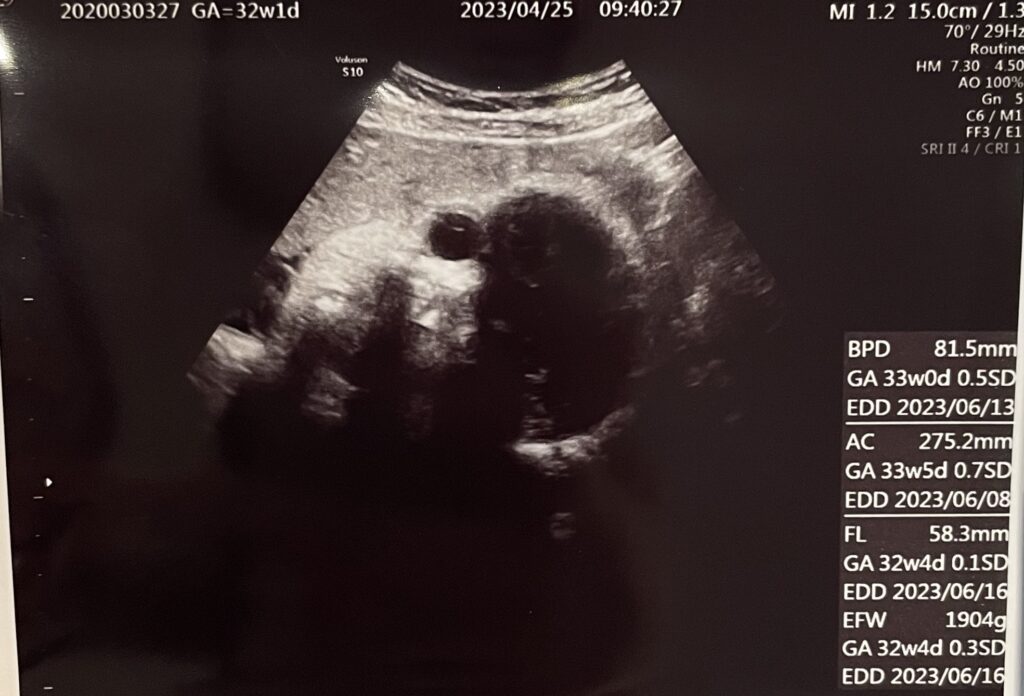

本日のメインイベント!赤ちゃんの頭の位置を確認する会です。(エコー)

結果はというと、頭が下にきていました!

体重も1904gと順調に増えてきています。最終的にどのくらいになるのかも楽しみです。